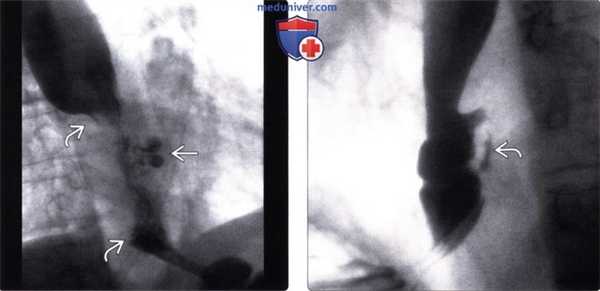

(Слева) На рентгенограмме пищевода определяется тугая стриктура в области пищеводно-желудочного перехода. Т. к. наличие такой стриктуры является подозрительным на метаплазию Барретта или рак пищевода на ранних стадиях, была выполнена баллонная дилатация и пищевода.

(Справа) На рентгенограмме, полученной у этого же пациента после биопсии, в стенке пищевода на ограниченном участке визуализируется скопление контрастного вещества, что означает неполную перфорацию стенки. В подобных случаях излечение обычно происходит самостоятельно. (Слева) На рентгенограмме пищевода, выполненной мужчине 62 лет, у которого после лапароскопической операции по поводу ГПОД появились боли в грудной клетке и лихорадка, визуализируются внепросветные скопления газа и контрастного вещества в средостении и в брюшной полости.

(Справа) На аксиальной КТ с контрастным усилением у этого же пациента также визуализируются скопления газа и контрастного вещества в средостении и брюшной полости, означающие перфорацию стенки возле пищеводно-желудочного перехода. В этом случае пациенту потребовалось хирургическое вмешательство и дренирование, завершившееся успешно.